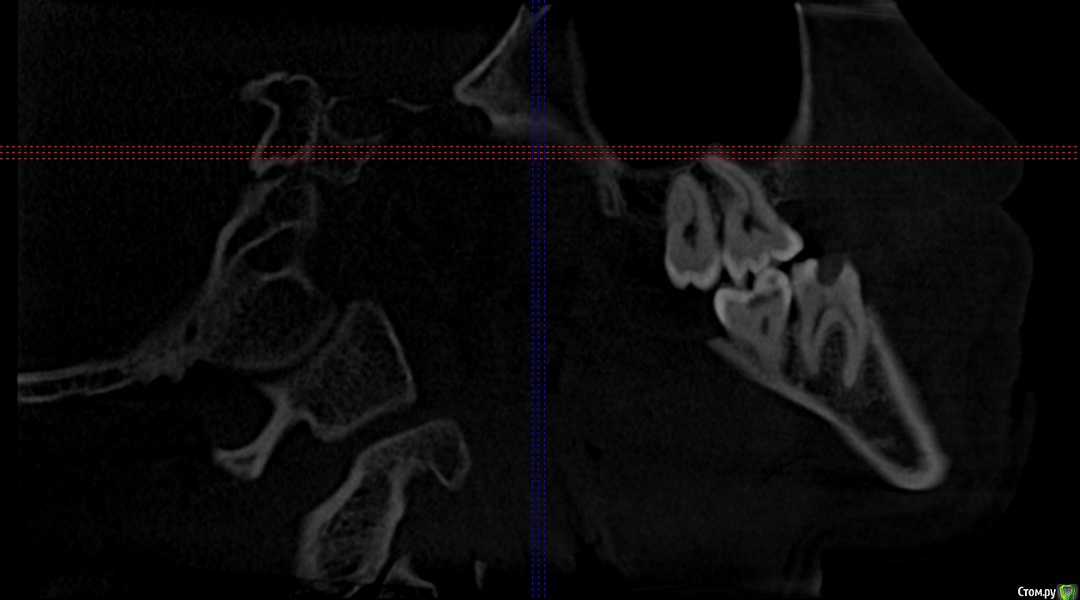

Секатор Опубликовано 4 октября, 2015 Поделиться Опубликовано 4 октября, 2015 (изменено) Здраствуйте,уже писал,но проблем много,но сча есть снимки зд(ссори за флуд).Начну издалека года два летом примерно неделю начили болеть зубы справа с отдованием в ухо и висок,оперативно ничего не делал(спас ал алкоголь),но я решил,что это 8-ки,и за зиму последнию все удалил,но отдования в висок и болезненность уха осталось,много времени прошло после удаления.Напряжение у виска и в области уха,взгляните на мою 6 справа,дно пазухи деформировано под её давлением,боли в области зуба нет-она причина?По лор все чисто,как будто болит зуб отдовая в ухо и висок,но без боли в области челюсти.Ближе к внутренней стенки пазухи и заходя на неё сформирован остроконечный конус дном пазухи,вследствии давлении корня зуба. Изменено 4 октября, 2015 пользователем Секатор 1 Ссылка на комментарий

Секатор Опубликовано 15 октября, 2015 Автор Поделиться Опубликовано 15 октября, 2015 (изменено) И,ещё раз прошу взглянуть смотрите,как деформирована внутреннеяя стенка пазухи зубом,у дна.Может корень подцепил,стенку пазухи? Изменено 15 октября, 2015 пользователем Секатор Ссылка на комментарий